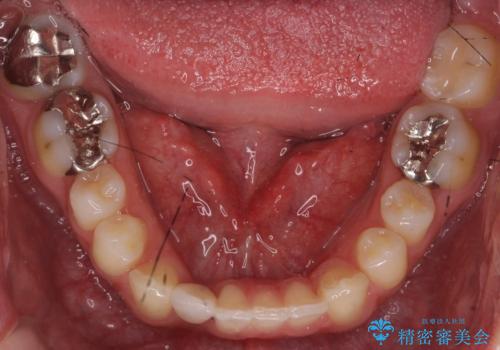

下の前歯のインプラント 生まれつき歯が少ない

- 下の前歯が1本生まれつき少なかったため、インプラント治療を行いました。

インプラントの前に矯正治療を行い、入れる隙間を確保しました。

ブリッジにすることも可能でしたが、両側の歯が天然歯であること、また、事前に矯正で噛み合わせを整え、幅も確保していたこと、CTにより骨の厚みがある程度あったことを踏まえ、インプラントも可能であるとお話しし、選んでいただきました。

唇側の骨増成もしっかり行い、前歯部インプラントによくある、歯茎が下がって見えることもない、審美的なインプラント補綴ができました。